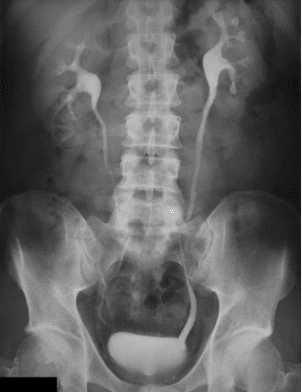

Professor A was tall, thin, easy-going, and a chain-smoker. Professor B was shorter, stouter, older, and seemed to like yelling (in our lectures, anyway). There was no way to know in advance who would be “interrogating” (that is the word we used) me. Probably whichever professor was free when a student showed up at the appointed time would be the examiner. I walked into the urology office and saw Professor A and Professor B. “Sit down,” Professor A invited, and grabbed a few intravenous pyelograms that were on his desk. These are X-ray examinations that use an injection of contrast material (“dye”) to evaluate the state of the kidneys, ureters, and bladder.

He showed me one and asked what I saw. I told him that there was a filling defect in one of the ureters, that is, an area where no dye was visible. “Yes, and what could that be?” he asked. “Well,” said I, “something is occupying some space in the ureter. It could be a stone, or a tumor, or . . .” Professor A nodded agreement, while professor B shouted, “No!” and gave some reasons why it was not so. I do not remember what they were; this was forty-five years ago. When the two professors started arguing with each other, I was forgotten and sat there silently.